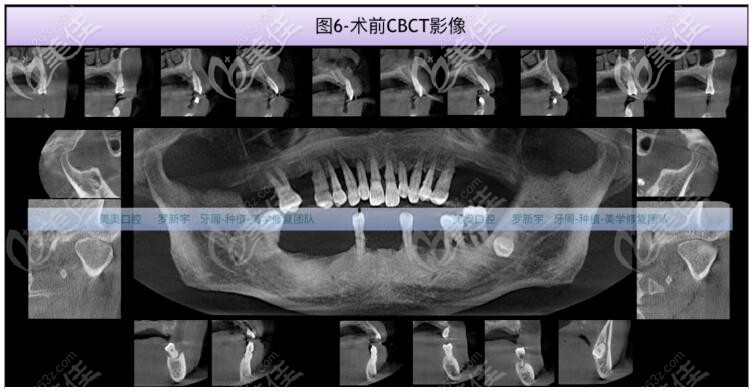

在羅醫(yī)生的面診,結(jié)合CT拍片檢查,大爺?shù)娜毖绤^(qū)骨質(zhì)II-III類,骨量充足,但15、14、13、12、11、21、22、23、24、25、37、36、48中到重度骨吸收。17、33、43輕中度骨吸收。